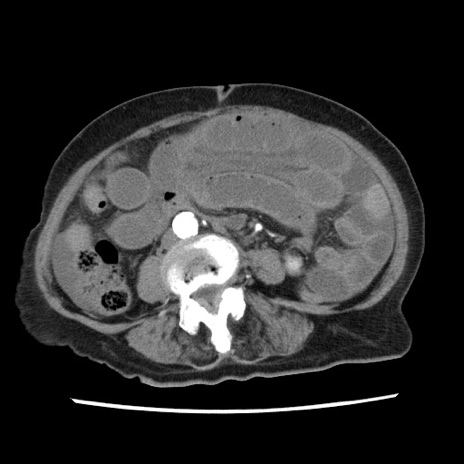

症例1(横断像)

【症例】80歳代女性

【主訴】腹痛

【現病歴】8時間前から腹痛あり来院。

【既往歴】糖尿病、脂質異常症、子宮体癌にて子宮全摘術

【身体所見】意識清明・会話良好だが腹痛で苦悶様、全腹部にわたって反跳痛と圧痛あり

【データ】WBC 13600、CRP 0.14、LDH 224、CK 90